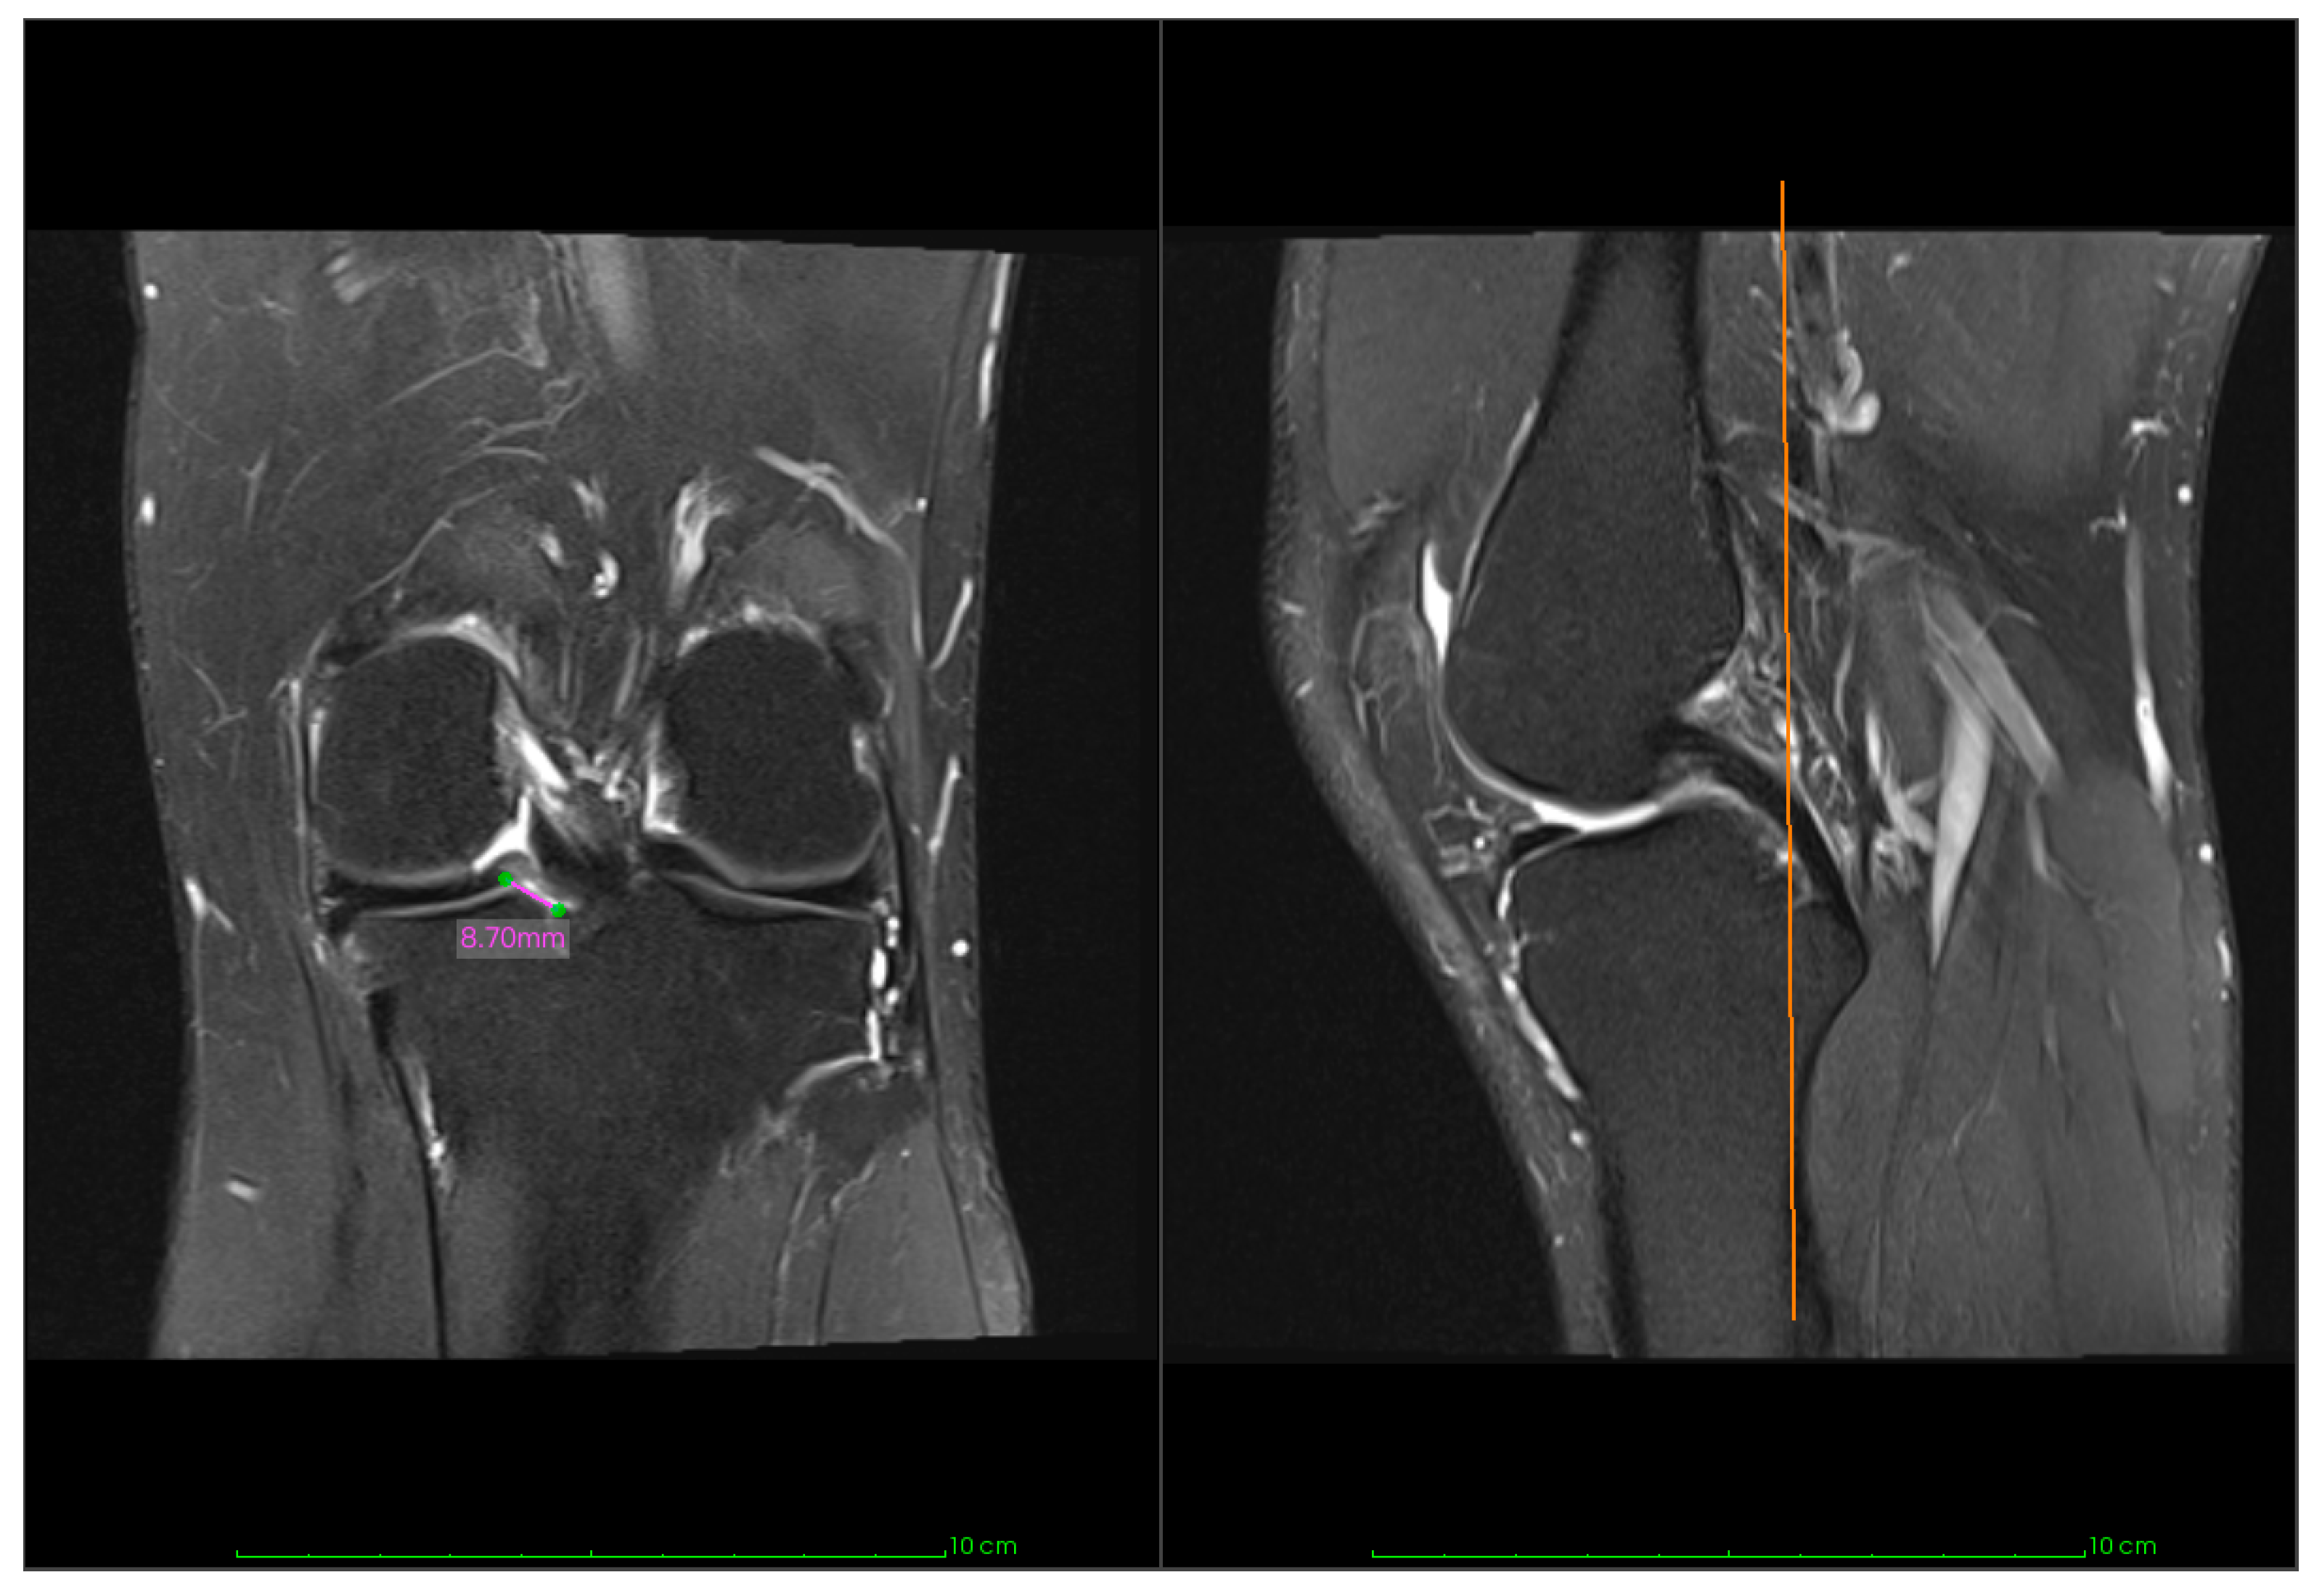

| ME preoperative (mm) | 10 | 3.32 ± 1.77 |

| ME postoperative (mm) | 10 | 3.94 ± 1.72 |